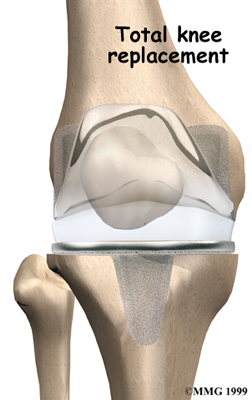

Artificial Knee Replacement

An artificial knee replacement is the ultimate solution for advanced knee OA.

Surgeons prefer not to put a new knee joint in patients younger than 60. This is because younger patients are generally more active and might put too much stress on the joint, causing it to loosen or even crack. A revision surgery to replace a damaged prosthesis is harder to do, has more possible complications, and is usually less successful than a first-time joint replacement surgery.

Related Document: FYZICAL Westchase's Guide to Artificial Joint Replacement of the Knee